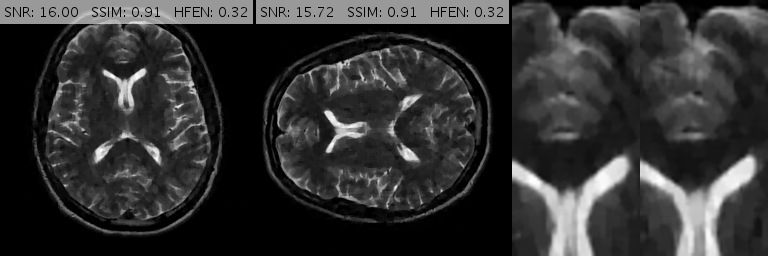

Fig. 10 shows the performance of various algorithms for a sagittal head scan reconstruction under 16% spiral sampling. The solutions provided by pFISTA and TL miss much of the image content due to over-smoothing. TGV+Shearlet leaves many incoherent artifacts on all regions. The magnified views obviously show that BM3D degrades the image by leaving block artifacts around the cerebellum and streaking artifacts on the medulla and the visual cortex. DAMP, GBRWT, ADMM Net and FDLCP provide more accurate results, however, by inspecting the magnified views it becomes evident that some small artifacts are introduced in DAMP near the caudate nucleus and beneath the cerebellum while a dark hole at the center of the cerebellum has been almost entirely smoothed out by the other three methods. The proposed method (labeled ‘New’) accurately captures this hole and corrects all the errors mentioned above.

Fig. 13 demonstrates various reconstructions for an axial -weighted brain image under a 20% Cartesian sampling. The magnified views show that FDLCP has smoothed out fine cerebral details while DAMP, ADMM Net, GBRWT, pFISTA, TL and TGV+Sh have introduced severe artifacts into the image, not least among them is a very large dark hole in the parietal lobe. BM3D provides a better result but this method also degrades the ventricles. The proposed framework again gives the best result with the cleanest error map.

For convenience, in Figs. 10, 11 and 13 we have inserted the SNR, SSIM and HFEN values for each method to the top of the corresponding reconstructed image. Moreover, some reconstruction errors in compared methods and their corrections in the proposed method are annotated with arrows.